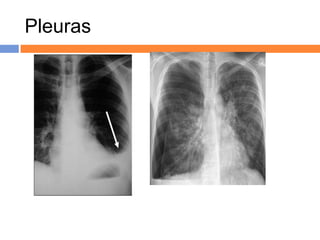

Pleuras

Derrames pleurais, loculado (E) e

livre (D, com sinal do menisco).